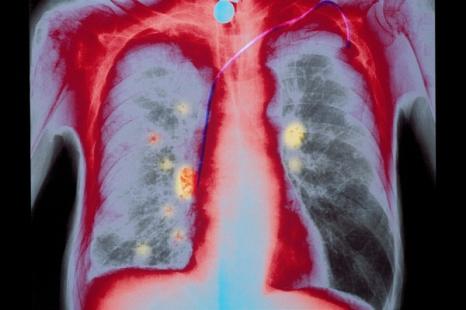

Tedopi est un vaccin contre le cancer du poumon non à petites cellules (CPNPC) avancé ou métastatique, développé par la biotech française OSE Immunotherapeutics. Il réduirait de 41 % le risque de décès par rapport à la chimiothérapie.

Tedopi est un vaccin thérapeutique ciblant cinq antigènes tumoraux permettant l’activation des lymphocytes T spécifiques de la tumeur.